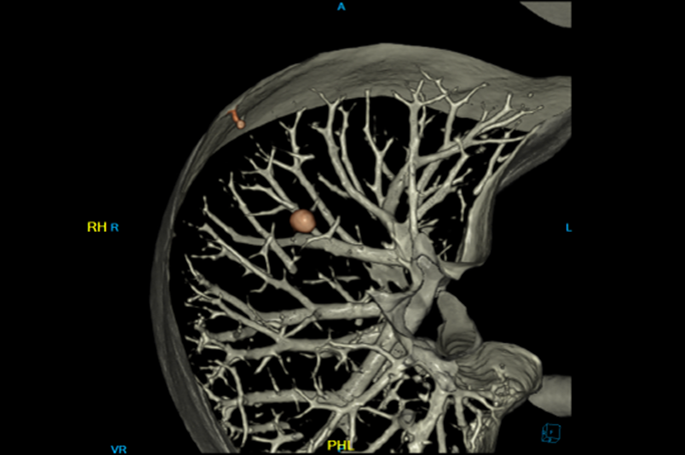

Cardiac Function

ECG Built in system

Cardiopalmus “FROZEN” Technology

0.32s(RTF)Cardiac Scan / one rotation

128 Slices CT – Designed for Cardiac Scan

• Fast 0.32 sec Cardiac Scan

• ECG integrated in the Gantry

• 60msec Cardiac Temporal Resolution

• Prospective Gating or Retrospective Gating with up to four sectors